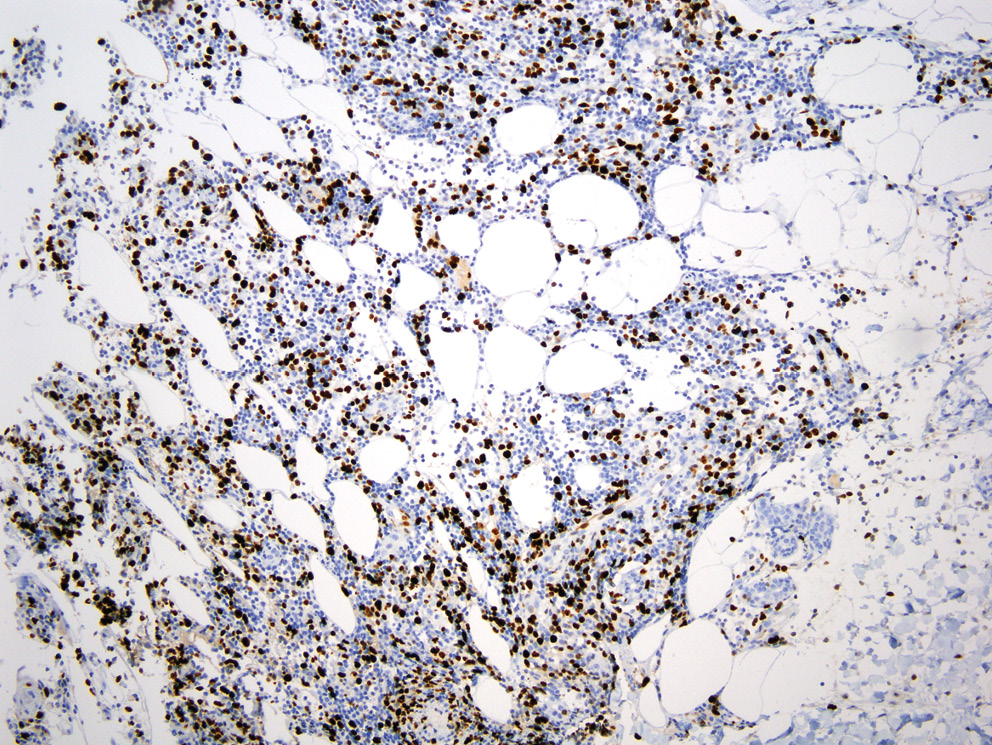

Учитывая отсутствие в биоптате признаков васкулита, гистологический материал пациента был направлен на пересмотр в НИИ онкологии им. Н.Н. Петрова, где было выполнено иммуногистохимическое исследование с антителами ALK, DSF3, CD3, CD4, CD8, CD20, CD30, CD56, Ki-67. По результатам исследования в дерме определялись плотные крупноочаговые инфильтраты, расположенные преимущественно в средних и глубоких отделах дермы и проникающие в дольки подкожной жировой клетчатки (рис. 3). Инфильтраты состояли из крупных лимфоидных клеток с иммунобласто- и центробластоподобной морфологией (рис. 4) и малых лимфоцитов. Крупные лимфоидные клетки экспрессировали CD3+, CD4+ и CD30+, были негативны к ALK (рис. 5–7). Ki-67 (индекс пролиферативной активности) был положителен преимущественно в крупных лимфоидных клетках и составлял примерно 30% всех клеток инфильтрата (рис. 8). Гистологические изменения и иммунофенотип опухолевых клеток соответствовали ЛиП типу С.

Рис. 8. Микрофотография, ×40, иммуногистохимическое исследование на определение экспрессии Ki-67. Экспрессия маркера Ki-67 определялась преимущественно в крупных лимфоидных клетках, которые составили примерно 30% всех клеток инфильтрата

Fig. 8. Microphotograph, ×40, immunohistochemical assay to determination of Ki-67 expression. Expression of Ki-67 was positive predominantly on lare lymphoid cells which accounted for approximately 30% of infiltrate